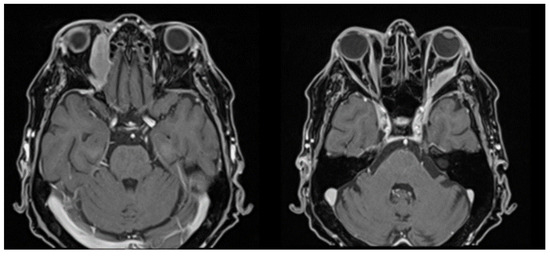

| January 2023 | second extramedullary relapse bilateral ocular left eye clinically, imaging, and biopsy demonstrated right eye demonstrated by imaging | methotrexate, asparaginase, calcium folinate radiotherapy, 30 gy/15 sessions result: imaging complete remission |